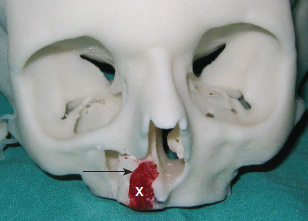

70 ○ Patient selection for alveolar transport distraction osteogenesis and its ultimate success involve patient motivation, parent and patient commitment to the procedure and postoperative course, and excellent oral hygiene. ○ Preoperative planning using three-dimensional imaging and models to execute the projected movements is vital to confirm ultimate segment positioning and stability. ○ Local tissue health and integrity with enough attached gingiva for final “docking” of the distracted segment and bone grafting of the defect is necessary before initiating distraction. ○ The reconstruction team consists of a surgeon, an orthodontist, and a restorative dentist (prosthodontist) who agree on the plan and timing for distraction. ○ Simultaneous anterior maxilla and piriform distraction can be achieved through distraction of a larger dentoalveolar segment, thus augmenting these regions, with or without grafting. Management of the alveolar cleft defect (ACD) has often been a challenging aspect of the comprehensive management of patients with orofacial clefts. The ACD results from intentional delay in treatment or failed attempts at repair during primary cleft lip or palate surgery. Typically, ACDs result in a collapsed, disunited arch with unsupported lip, nasal, and dental elements. The concomitant oronasal fistula (ONF) contributes to sinonasal inflammation, drainage, and periodontitis. Therefore repair of the osseous defect and closure of the fistula are considered important aspects of complete cleft management. Fig. 70-1 A, Right unilateral cleft with wide, disparate alveolar segments. B, Right unilateral cleft with deficient soft tissue and a wide bony defect. Repair of the ACD has a long history in cleft care. The goals for adequate treatment include1,2: Attempts at ACD closure by performing gingivoperiosteoplasty at lip repair have been met with varying results, oftentimes necessitating future formal repair with bone grafts. The timing of ACD repair also has been controversial. Primary osteoplasty, with placement of autogenous bone at or near the time of initial lip repair, has been both condemned and championed. Many results have been less than ideal, again with the need for further bony augmentation of the alveolar segment.3–5 Secondary osteoplasty of the ACD is considered the treatment of choice for many cleft teams, principally because it is predictable and achievable, satisfying the goals of repair as stated previously. Early secondary osteoplasty, as advanced by Boyne and Sands6 as well as others, attempts to graft the ACD before eruption of the permanent incisors.7,8 Delayed secondary osteoplasty has been shown to be effective and predictable for most children when it is performed before the complete root formation of the adult canine tooth, around 10 to 12 years of age.9,10 Delayed secondary osteoplasty is usually performed in conjunction with preparatory orthodontics and after some orthopedic manipulation to optimally position the cleft segment. However, a significant number of patients experience failed bone graft procedures, have very wide defects with collapsed cleft segments, or have significantly scarred ACDs with questionable soft tissue covering, all of which make further attempts at bone grafting rather dubious and unsatisfying. This is aptly termed recalcitrant ACD (Fig. 70-1) and is especially challenging in particular circumstances: a lack of healthy unscarred mucogingival tissue lining the ACD, deficient alveolar bone height and width against which the graft must be placed, older patients with decreased bony healing potential, and the presence of compromised dentition or prostheses with little bone support.11 Recently, distraction osteogenesis (DO) has been developed for application in the craniofacial region. Smaller regional areas of the facial skeleton have been distracted to optimize functional and aesthetic units for future orthopedic or orthodontic correction, grafting procedures, or prosthodontic rehabilitation. In 1905, Codivilla12 initially described the concept of DO to lengthen a femur, correcting a limb length discrepancy. In the 1950s, this application was more widely applied to orthopedic limb lengthening. The landmark research into this technique by Ilizarov13 looked at the development of distraction techniques, devices, and rates on bone formation. He developed the technique on canine long bones and then applied the protocol to human patients, pioneering many of the concepts of DO, including recommendations on latency, distraction rate, and distraction rhythm. In 1992, McCarthy14 applied DO to the unilateral mandibular deficiency found in hemifacial microsomia. He lengthened the affected mandible in children using an external fixation device, which allowed calibrated distraction between external pins holders. At the completion of the distraction phase, the mandibles were stabilized for a mean period of 9 weeks. DO of the midface region has been performed by devices categorized as internal or external devices. Several maxillary DO devices have been used to advance the maxilla through either various osteotomies at the LeFort levels or segmentation of the maxilla.15 These procedures are discussed in Chapters 73 and 74. To achieve maxillary arch widening, Bell and Epker16 used a DO technique of rapid palatal expansion with a tooth-borne expander, increasing the transverse dimension of the maxilla after osteotomies had been performed. Guerrero and Bell17 further developed these techniques, using incremental expansions of 1 mm every other day, up to a total of 10 mm, to obtain significant transverse expansion of the arch. This concept was applied to the alveolar segment by Chin and Toth,18 who looked at regenerating alveolar bone after trauma using an internal distraction device with a transmucosal activation screw. Block and Baughman19 further applied DO to the vertically deficient alveolar segment, increasing bone height before implant placement. Simultaneous secondary bone grafting was performed in many of these cases after final alveolar segment distraction. Use of alveolar distraction is now widespread for preprosthetic manipulation before rehabilitation.20 Cleft alveolar distraction has been performed and studied by Liou et al,21 who used various osteotomies and appliances to approximate cleft segments, narrow the ACD, and improve arch dimension. Others also have applied DO to correct various cleft-related problems, such as a narrow or collapsed maxillary arch and a wide ACD with insufficient soft tissue, and to prevent bone grafting an ACD.22–25 Distraction has become an important tool in the management of particularly difficult or recalcitrant ACDs, discussed later in detail. Several indications for alveolar transport DO exist. A very wide ACD may preclude a bone graft if soft tissue and alveolar bone are deficient (see Fig. 70-1). A patient who has had a previous failed bone graft may be considered for transport DO to achieve the goals of standard alveolar cleft surgery (Fig. 70-2). Older patients who have not been treated for their ACD may be candidates for transport DO to narrow the defect and thus require minimal secondary grafting, improving the success for prosthetic rehabilitation. Fig. 70-2 A, A failed primary osteoplasty with a persistent defect. The failed bone graft was done at age 1. The patient has a fistula and insufficient osseous support for dental structures. B, Partial osteoplasty of a bilateral cleft defect with failure of the graft on the patient’s right. C, A patient with a partial osteoplasty on the left and complete failure on the right side. Alveolar cleft defects are, by nature, multidimensional, and have different defect combinations including the anteroposterior, horizontal, and vertical dimensions. Depending on the specific defect, transport DO may be considered for definitive treatment or to address the largest dimensional deficiency, thereby improving the quality and quantity of alveolar bone. This will allow for an easier and minimal secondary bone graft procedure. This process is particularly applicable when treating vertical alveolar deficiency. Vertical alveolar DO may be considered to increase alveolar bone height after grafting and when planning placement of an implant for later prosthetic rehabilitation. Several contraindications to alveolar cleft DO exist. A surgeon should be wary of initiating alveolar DO for patients with clefts who have not been compliant in various aspects of their treatment. DO is a very labor-intensive process, requiring a great deal of cooperation from the patient and caregivers; therefore education is crucial before initiating treatment. Patients with active dental issues should have these addressed, with consideration given to optimizing oral health before surgery. Periapical disease should be eliminated to prevent infection during the distraction period. In patients younger than 10 years of age, the potential exists for damage to developing teeth and impairing the eruption pattern in the area of distraction. This needs to be thoroughly discussed with the patient and family beforehand. Indirectly associated with compliance are the patient’s general health and condition of the local tissues. If any concern exists related to these areas, avoiding this mechanically technical procedure and the potential subsequent complications of tissue breakdown and loss of the device may be prudent. Children who have poorly controlled chronic asthma or allergies, resulting in nasal obstruction and patterns of mouth breathing that increase oral tissue inflammation, may be prone to intraoral tissue compromise and breakdown. For these reasons, optimal intraoral health should be maintained through primary care and pediatric dental management. Once these concerns have been satisfied, then plans for distraction can be undertaken. Fig. 70-3 An acrylic model of a right unilateral cleft defect (X) demonstrating planned distraction of the alveolar segment (arrow). As with all aspects of comprehensive cleft care, management of the ACD benefits from a team approach. Preparing the patient and family for the various aspects of therapy is important before initiating alveolar transport DO. In addition, coordination of the team involved in perioperative management is essential. The patient’s pediatric dentist should be involved well before transport DO is considered to optimize oral health before surgery. Any carious lesions should be addressed and periodontal disease eradicated before the patient is assessed for surgery. Questionable or nonvital teeth should be treated before DO is begun to eliminate the possibility of infection jeopardizing the distraction process. Orthodontic consultation and management is important to address dental and arch discrepancies before the repair of the ACD, whether by conventional bone grafting or by movement of the alveolar bone using distraction. The arch may require expansion before formal repair of the alveolar cleft, and the orthodontist must be involved in the planning and management during distraction. Finishing dental and arch alignment is the orthodontist’s responsibility. Prosthodontic management of the patient may be required postoperatively for the replacement of missing teeth. This may involve the placement of crowns or bridges, or the surgical placement of implants if bone stock is adequate. The patient must appreciate that grafted bone must be completely mature before implants can be placed, a period of approximately 3 months.26 Consultation with the prosthodontist is important to evaluate the arch space and bone height that will be needed for prosthetic rehabilitation. Three-dimensional acrylic models (Fig. 70-3) are a great help to the treating team, patient, and caregivers who will be involved in the distraction process. Precise placement and activation of the device can be achieved and demonstrated. The caregivers need to be instructed in the cleansing and hygiene of the activation rod. Perioperative antibacterial mouth rinses (oral chlorhexidine) and oral antibiotics should be carefully reviewed and dispensed. Pain medications and dietary instructions will need to be adjusted based on individual patient needs. Most children will have adequate analgesia with ibuprofen, which may be administered before or after each distraction event, as indicated. It is important to instruct the patient and caregivers about the objectives of DO and to create realistic expectations for what can be achieved. Instructions for care may have to be given in stages and over several preoperative appointments to establish a thorough understanding before and during treatment. The patient and family need to appreciate that DO may not be able to completely correct the anatomic deficits. Further surgery, in a second stage, will be required to remove the distractor; at that time, the defect can be simultaneously augmented with additional bone graft if necessary. As in many ACD reconstructions, final and acceptable soft tissue coverage may be required in a separate procedure to provide adequate attached gingiva around the teeth and implants. Vital to the success of any intraoral surgical procedure, particularly around the dentition and any abnormal anatomy, is optimal soft tissue composition and health. Loss or limitation of healthy keratinized tissue around the dentition may compromise the general integrity of the periodontium, leading to further bone loss or predictable bony surgery in the future. Studies have demonstrated that patients with cleft lip or palate have more periodontal compromise in the cleft defect area, including loss of a zone of healthy keratinized tissue.27,28 Although loose (unattached) mucosa may serve as a temporary healing or covering measure, such as labiobuccal mucosa grafts placed during primary or early secondary osteoplasty, this does not serve well for periodontal integrity in the long term. If plans are made for segmental osteotomy or distraction of a cleft segment, healthy abutting transposed attached (keratinized) tissue, both palatally and labiobuccally, is preferable. Soft tissue inadequacies such as these are seen especially in older cleft patients who have undergone multiple procedures, resulting in compromised soft tissue in and around the alveolar cleft defect and dentition.29 If a lack of healthy soft tissue is determined during the evaluation process, then plans should be made to graft the area to provide this tissue. Autologous graft from the palate (preferred) or acellular dermis graft can be placed in the immediate defect area and periodontium.30 After a period of maturation, variably 8 to 12 weeks, when keratinization is complete and inflammation resolved, subsequent bony surgery can be undertaken. When juxtapositioning the alveolar segments during final distraction, flap elevation and coverage of the bone graft should be easier and final closure more predictable with appropriately healthy mucogingiva. Unilateral ACDs are more common and often have problems with significant asymmetry and excessive defect width. Although skilled interceptive orthodontics can often successfully align and position the lesser segment and narrow the defect width, occasionally the poorly positioned cleft segment will remain, with suboptimal soft tissue that would compromise, and potentially prohibit, orthodontic treatment. A typical case is illustrated in Fig. 70-4. This patient had a long history of cleft surgical procedures, as well as two phases of orthodontics. The ACD was still poorly positioned with extensively scarred soft tissue; the radiographs verified a significant bony defect width between the segments. This situation is difficult to correct with conventional orthodontic preparation and alveolar bone grafting; therefore distraction of the cleft segment, to narrow the defect by approximating the alveolar segments, will increase the success of a smaller bone graft. A single vector alveolar distractor was placed on the buccal aspect of the lesser segment after vertical osteotomy between the bicuspids and horizontal osteotomy, approximately 7 to 8 mm above the level of the root apices. The activating rod is oriented in a favorable position under the lip for easy access. Postdistraction photos demonstrate an alveolus more favorably positioned for bone grafting. Many alveolar distractors offer various distracting lengths (10 to 20 mm) and multiple options for plate and screw placement (Fig. 70-5). The device should be contoured to the alveolar surface so that activation will move the segment in the desired direction. Some distractors allow for orientation of the activation rod from 0 degrees (coaxial to the distractor) to 30 degrees to allow favorable rod positioning and access for daily activation. Minimal activation should be performed during the surgical procedure to prevent undue tension on the overlying soft tissue, which may tear and compromise vascularity. Two or three millimeters of activation, to confirm complete mobility of the osteotomized segment, will suffice at the time of distractor placement.